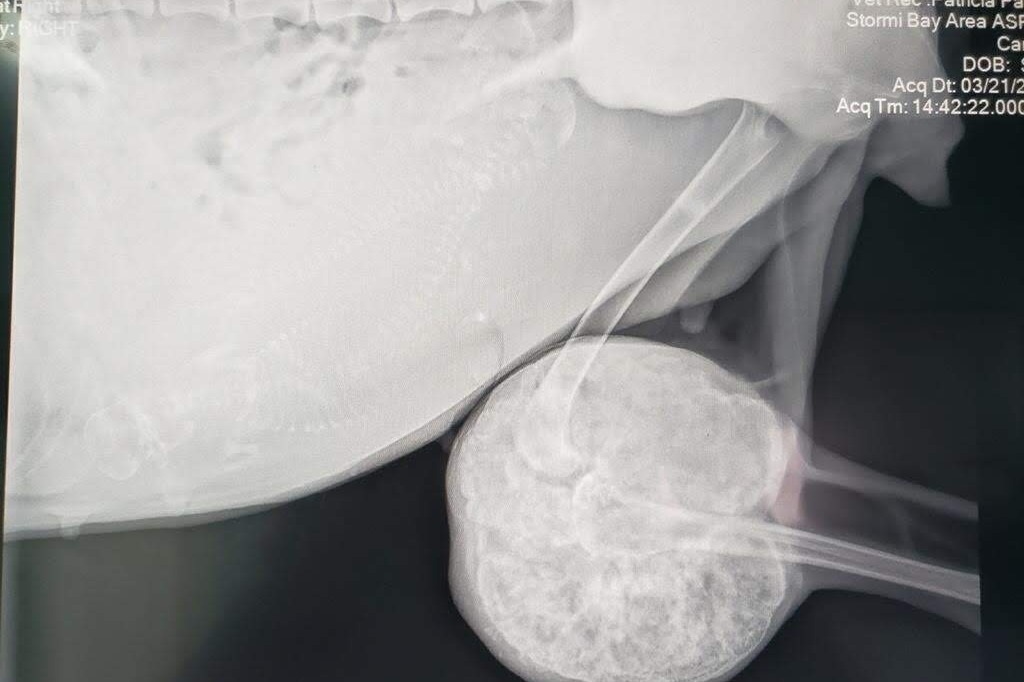

Skye, the young female gave birth to 3 male puppies four days after arriving at Bay Area Pet Adoptions and Stormi, the senior husky gave birth to 4 female puppies 6 days later. Upon x-ray it was determined that Stormi had a hard, circular mass the size of a large grapefruit that encompassed her knee. She is unable to use that leg and it is causing disfigurement of her spinal column. Amputation is needed for her to live comfortably.